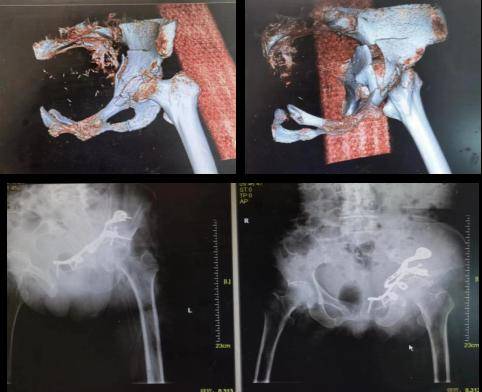

复杂骨盆骨折C型骨折、多发伤患者,膀胱破裂。失血性休克,情况凶险。通过一期损伤控制抢救生命,泌尿科膀胱修补造瘘,ICU监护生命支持,后期骨科前后路髋臼骨盆微创手术内固定等多学科救治,患者4周就可以恢复站立行走,体现了我院救治危急重症的综合能力。

装修工人高处坠落致复杂双柱髋臼骨盆骨折,手术较为复杂。科室通过前方腹直肌旁单一入路微创手术,就可以完成所有骨盆髋臼骨折的固定,骨盆正位显示术中良好的复位与固定。3年后患者恢复良好,仍能从事体力工作。